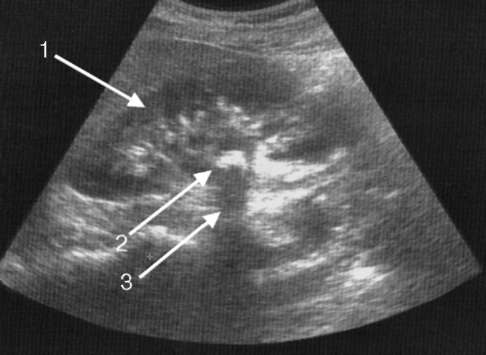

Картина эхоплотного образования без дорсального усиления характерна для наличия тканевой структуры с высокой отражающей способностью, такой как жир (липома), фиброзная ткань (фиброма) или смешанная структура (ангиомиолипома). Эхоплотная структура с формированием акустической тени свидетельствует о наличии кальция в выявленном образовании. Локализация такого образования в полостной системе почки или мочевыводящих путях говорит о имеющемся камне (рис. 4.14).

Рис. 4.14. Сонограмма. Камень почки: 1 - почка; 2 - камень; 3 - акустическая тень от камня